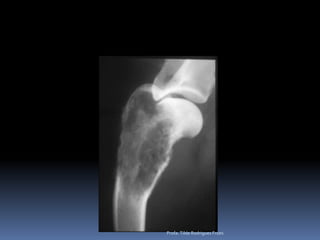

Exame radiográfico Esqueleto apendicular e axial“Achados radiográficos”Doença articular degenerativaEscápulo umeral (Achado radiográfico)Correlacionado a Displasia coxofemoral (relevância clínica)Espondiloses - COLUNA*Instabilidade lombosacral*Espondilomielopatia cervical*Doença do disco IV*DiscoespondiliteOsteoartrose do JoelhoProfa. Tilde Rodrigues Froes

Exame radiográfico Esqueleto apendicular e  axialImportanteAlta freqüência – NEOPLASIAS ÓSSEASEsqueleto apendicular e axialOSTEOSSARCOMAAspectos radiográficosDiferenciais diagnósticosNão esquecer – radiografar o tórax – metástasesCuidados nessa interpretação – falsos negativos – lesões iniciaisProfa. Tilde Rodrigues Froes

Como diferenciar lesões ósseas Esqueleto ApendicularMalignas BenignasTipo de reação periostealPouco delimitadasMais expansivasTipo de perda ósseaBordos pouco precisosPerda da integridade da corticalZona de transiçãoIndefinidaLocalPoliostica x monosticaPiora na avaliação seriadaTipo de reação periostealMais delimitadaMenos expansivasTipo de perda ósseaBordo definidoNão altera a integridade da corticalZona de transiçãoDefinidaLocal Profa. Tilde Rodrigues Froes

Animal:Rambo, canino, Rott, Macho, 10 anos, FC 901/10Profa. Tilde Rodrigues Froes